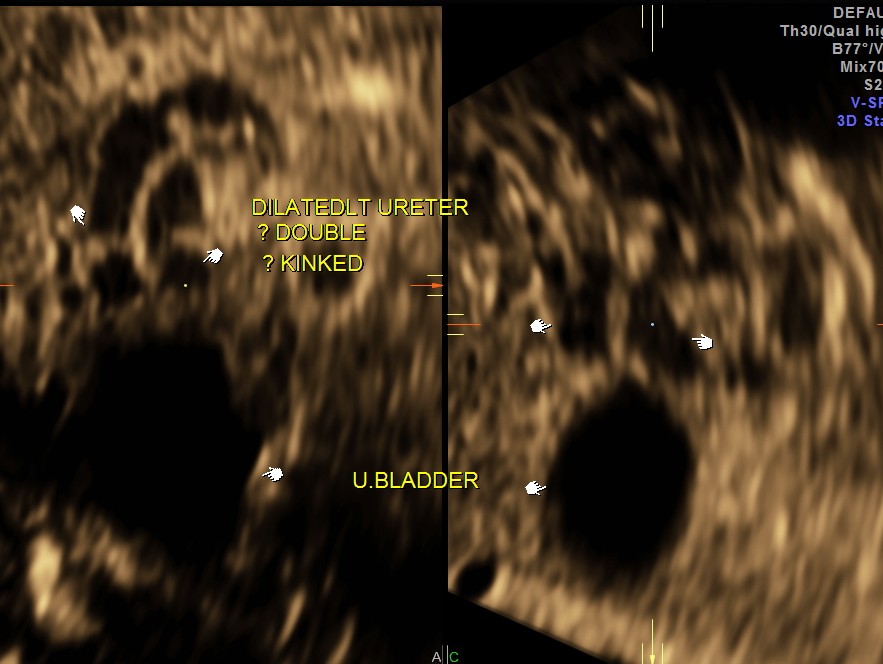

The following images show bilateral renal pelvi ectasis and bilateral dilated ureters with all the changes more in the left kidney .

The left kidney also showed possible duple-ix pelvis with double ureters arising from them . But this finding could not be confirmed in all the views .